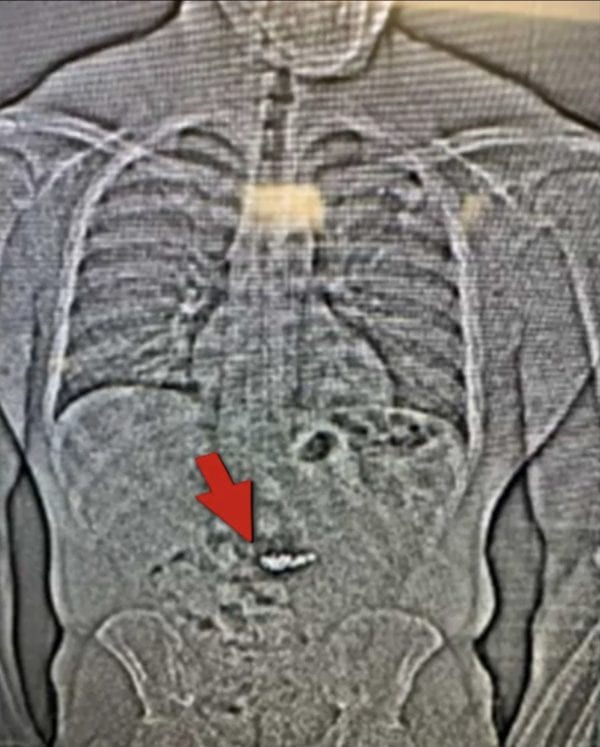

A scan at a nearby jail reportedly confirmed the presence of the suspected earrings inside Gilder’s stomach. Authorities stated that the items “will need to be collected after they are passed through Gilder’s system prior to confirming.”